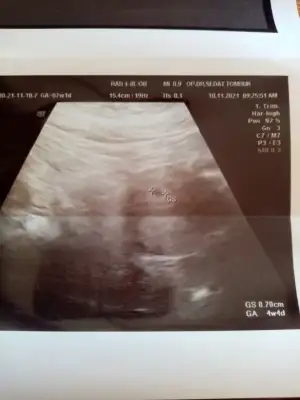

Canımm gözünaydn 😍bende şmdi cıktm doktor dan bizde minik bir kesecik gördükk doktor sıkıntı yok folikasite devam etmen yeterli dedi. Normal de sat a göre 7+1 olmam lazım ama ultrasona göre gec döllenme den dolayı 4+4 şuan 15 gün sonra gel kalp atışını duyarız dedi hayrlsyla inşallah 🙏 bana cm söylemedi ama Bi yorum yaparmsn tecrübeli anneler😂 😍

• 16365346523276824368198968838083.webp

16365346523276824368198968838083.webp

20,6 KB · Görüntüleme: 101